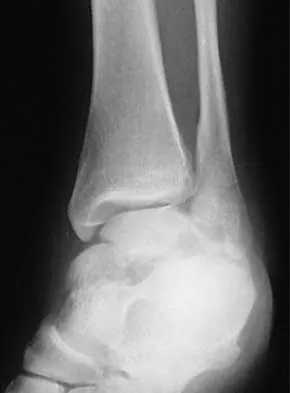

Figures 4a through 4c show the radiographs of a 43-year-old woman who sustained a twisting injury to her right ankle. She has ankle pain and tenderness medially and laterally. To help determine the optimal treatment, an external rotation stress radiograph of the ankle is obtained. This test is designed to evaluate the integrity of what structure?

Explanation

In the presence of a supination external rotation-type fracture of the distal fibula (Weber type B), stability of the ankle is best assessed by performing an external rotation stress AP view of the ankle. This test is used to assess the integrity of the deltoid ligament. The presence of a deltoid ligament rupture results in instability and generally is best managed surgically. The gravity stress test can also be used. Egol KA, Amirtharajah M, Tejwani NC, et al: Ankle stress test for predicting the need for surgical fixation of isolated fibular fractures. J Bone Joint Surg Am 2004;86:2393-2398. McConnell T, Creevy W, Tornetta P III: Stress examination of supination external rotation-type fibular fractures. J Bone Joint Surg Am 2004;86:2171-2178.